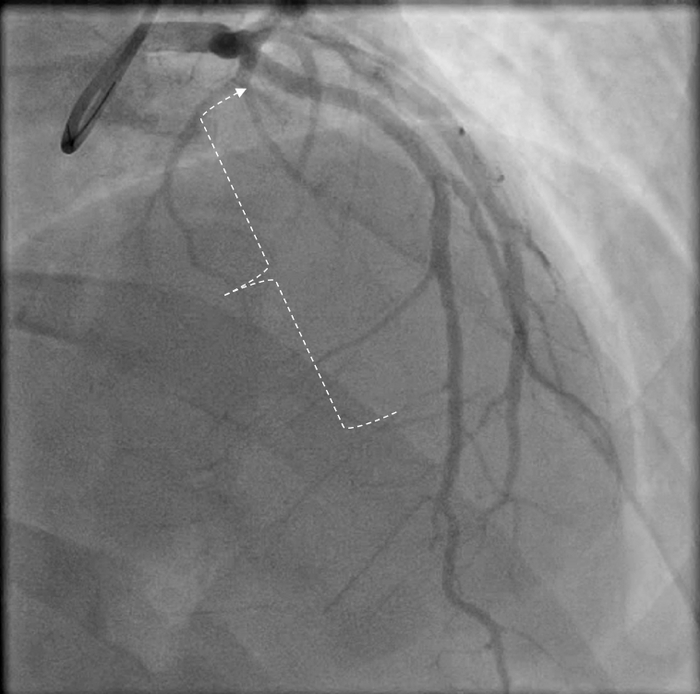

И что же там?? На коронарографии? Для краткости пару проекций (видео)

Пояснение - полная закупорка (стрелкой указано место где закрыт сосуд) передней межжелудочковой артерии - одна из самых важных в кровоснабжении сердца.

Скобками показан пораженный участком правой коронарной артерии (расслоение сосуда, вследствие надрыва стенки). Правая артерия часто вторая по значимости после передней.